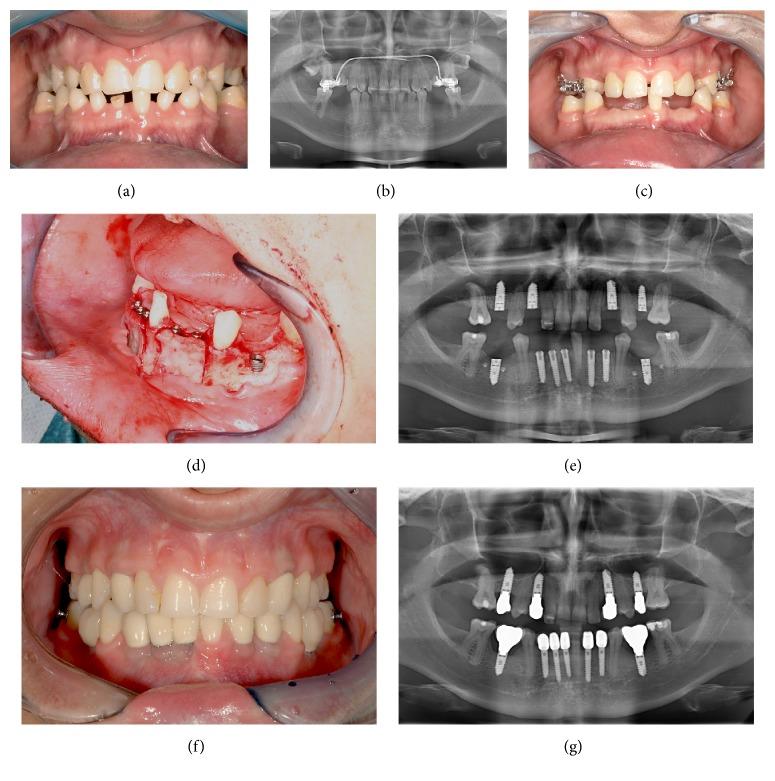

Forty-three patients were diagnosed with dental aplasia and treated with dental implants between November 2000 and February 2016. The variables assessed included the plaque level, bleeding on probing, probing depth, implant mobility, implant stability, and implant loss. To analyze the peri-implant bone level, a panoramic X-ray of each patient was taken. The results were compared with X-rays taken immediately after implantation.

Thirty-seven patients (16 males; 21 females) participated in this study. In total, 155 implants (86 maxillary; 69 mandibular) were inserted. Two of the 155 implants failed; the survival rate was 98.7%. The success rate according to the criteria of Buser et al. was 96.8%, and that according to the criteria of Albrektsson et al. was 88.4%.

2000 年 11 月至 2016 年 2 月期间,诊断出 43 名患有牙缺失的患者,并为其植入牙种植体。评估的变量包括菌斑指数、探诊出血、探诊深度、种植体动度、种植体稳定性和种植体丧失。为了分析种植体周围骨水平,对每位患者进行全景 X 光检查。将结果与植入后立即拍摄的 X 光片进行比较。

37 名患者(16 名男性;21 名女性)参与了这项研究。总共植入了 155 枚种植体(86 枚上颌;69 枚下颌)。其中 2 枚种植体失败,存活率为 98.7%。根据 Buser 等人的标准,成功率为 96.8%,根据 Albrektsson 等人的标准,成功率为 88.4%。